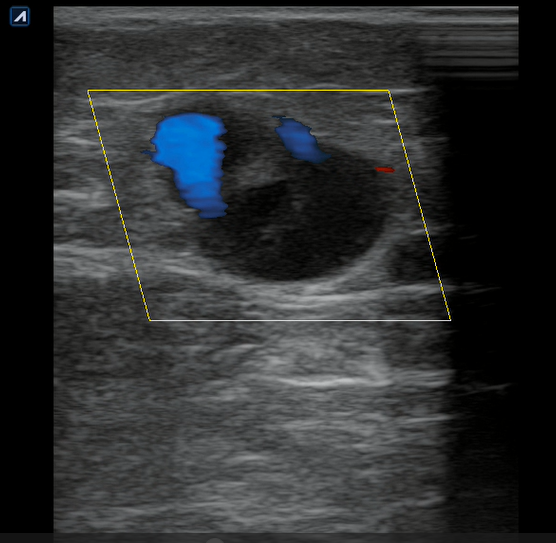

Se realiza ecografía clínica en consulta donde observamos a nivel inguinal adecuada compresibilidad de vena femoral y relleno con Doppler color. Cayado de safena libre y compresible. A 7 cm de distancia del cayado se aprecia, en territorio de safena, dilatación no compresible de la misma, contenido intraluminal ligeramente ecogénico y ausencia de Doppler color compatible con trombosis venosa superficial de 19 cm de distancia. Se estudia recorrido donde se observa en zona de dilataciones varicosas material ecogénico con ausencia de paso de Doppler alternando con zonas de paso parcial. En tercio distal de muslo comienza a desaparecer. Vena femoral profunda, poplítea y perforantes sin datos de trombosis.